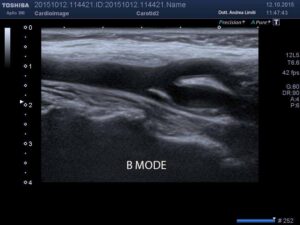

‘Ecocolordoppler dei vasi epiaortici, ossia delle arterie che portano sangue al cervello ed al volto, è una metodica di indagine che si avvale della combinazione dell’immagine ecografica unitamente alle informazioni fornite dall’uso del color doppler. L’esame consiste nell’appoggiare una sonda ai lati del collo e studiare quindi la morfologia ed il decorso dei vasi, la loro pervietà ( verificandone la presenza di eventuali placche ateromasiche più o meno occludenti l’interno dell’arteria ) ed il flusso di sangue verso il cervello. L’esame viene pertanto eseguito quasi esclusivamente per la valutazione della malattia aterosclerotica che, unitamente alla malattia delle piccole arterie ed alla cardioembolia, rappresenta la causa più frequente di ictus ischemico sia in prevenzione primaria ( ossia in soggetti che non hanno subito eventi cerebrovascolari ma ad alto rischio come possono esserlo i fumatori, i diabetici, gli ipertesi, i dislipidemici…) sia in prevenzione secondaria. Qualora sia già nota una ateromasia dei vasi epiaortici l’esame consente di monitorarne, nel tempo, il decorso ponendo indicazione ad eventuale intervento chirurgico di TEA ( endoarteriectomia carotidea ) o di stenting.